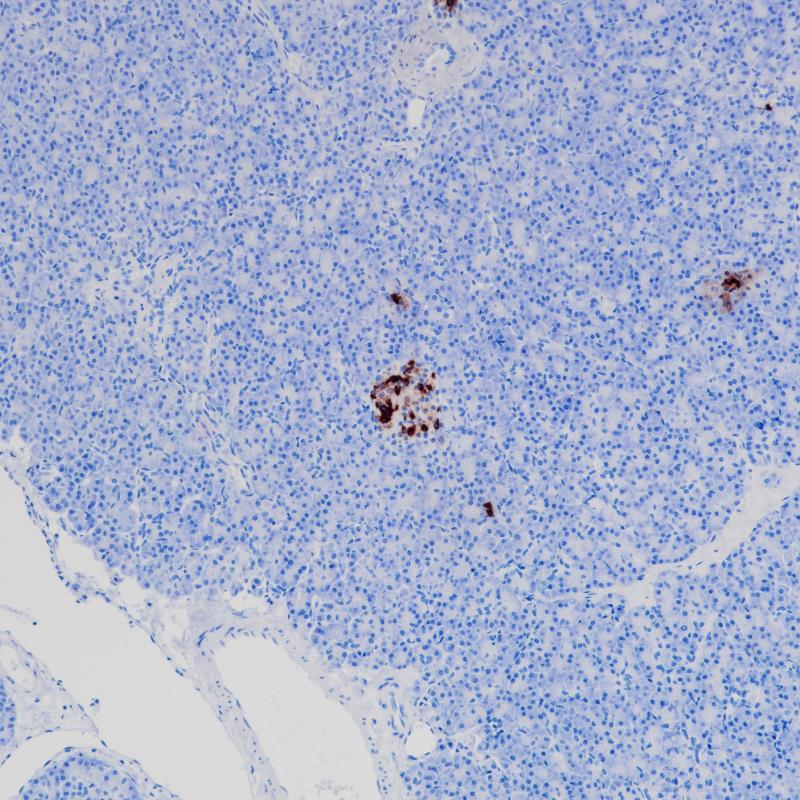

转录因子OVO-like zinc finger 2(OVOL2)包含一个C2H2锌指四分体的锌指结构域,具有可变的N端和C端延伸,起到转录调控的作用。OVOL2在维持上皮谱系的特性中起关键作用。它还通过直接抑制MYC和NOTCH1来抑制细胞周期和角化细胞的终末分化。OVOL2在人类正常组织的睾丸、卵巢、心脏和骨骼肌中表达。研究表明OVOL2是一种结直肠肿瘤抑制因子,通过阻断WNT信号传导来减少结直肠肿瘤的进展和转移。此外,OVOL2被证明可以直接抑制几种糖酵解基因的表达,阻断Warburg效应和乳腺肿瘤的生长和转移。

阳性对照

结肠癌

亚细胞定位

细胞核